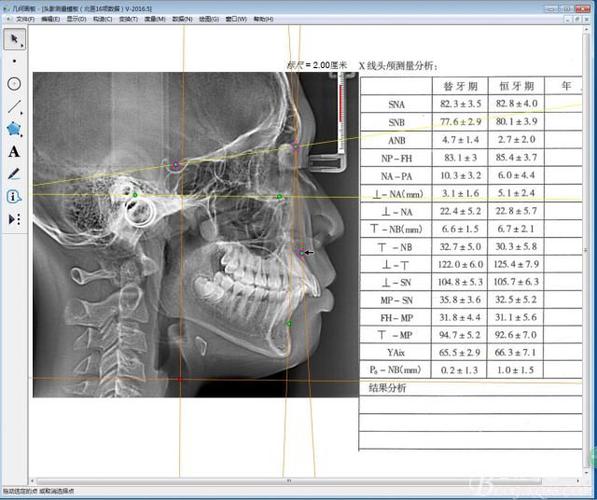

软件内置正畸测量数据库,可自动计算100余项指标,涵盖骨骼、牙齿、软组织三方面:

- 骨骼分析:SNA角(上颌骨位置)、SNB角(下颌骨位置)、ANB角(上下颌关系)、MP-FH角(下颌平面倾斜度)等,判断骨性错颌类型(如II类、III类错颌)。

- 牙齿分析:U1-NA角(上颌切牙突度)、L1-NB角(下颌切牙突度)、U1-L1角(上下切牙夹角),评估牙齿唇舌倾及拥挤度。

| 结果输出 | 生成头影描迹图、测量数据表、侧貌预测图;导出PDF报告。 | 报告中需标注正常值范围(如SNA角82±3°),便于非专业人士理解。 |